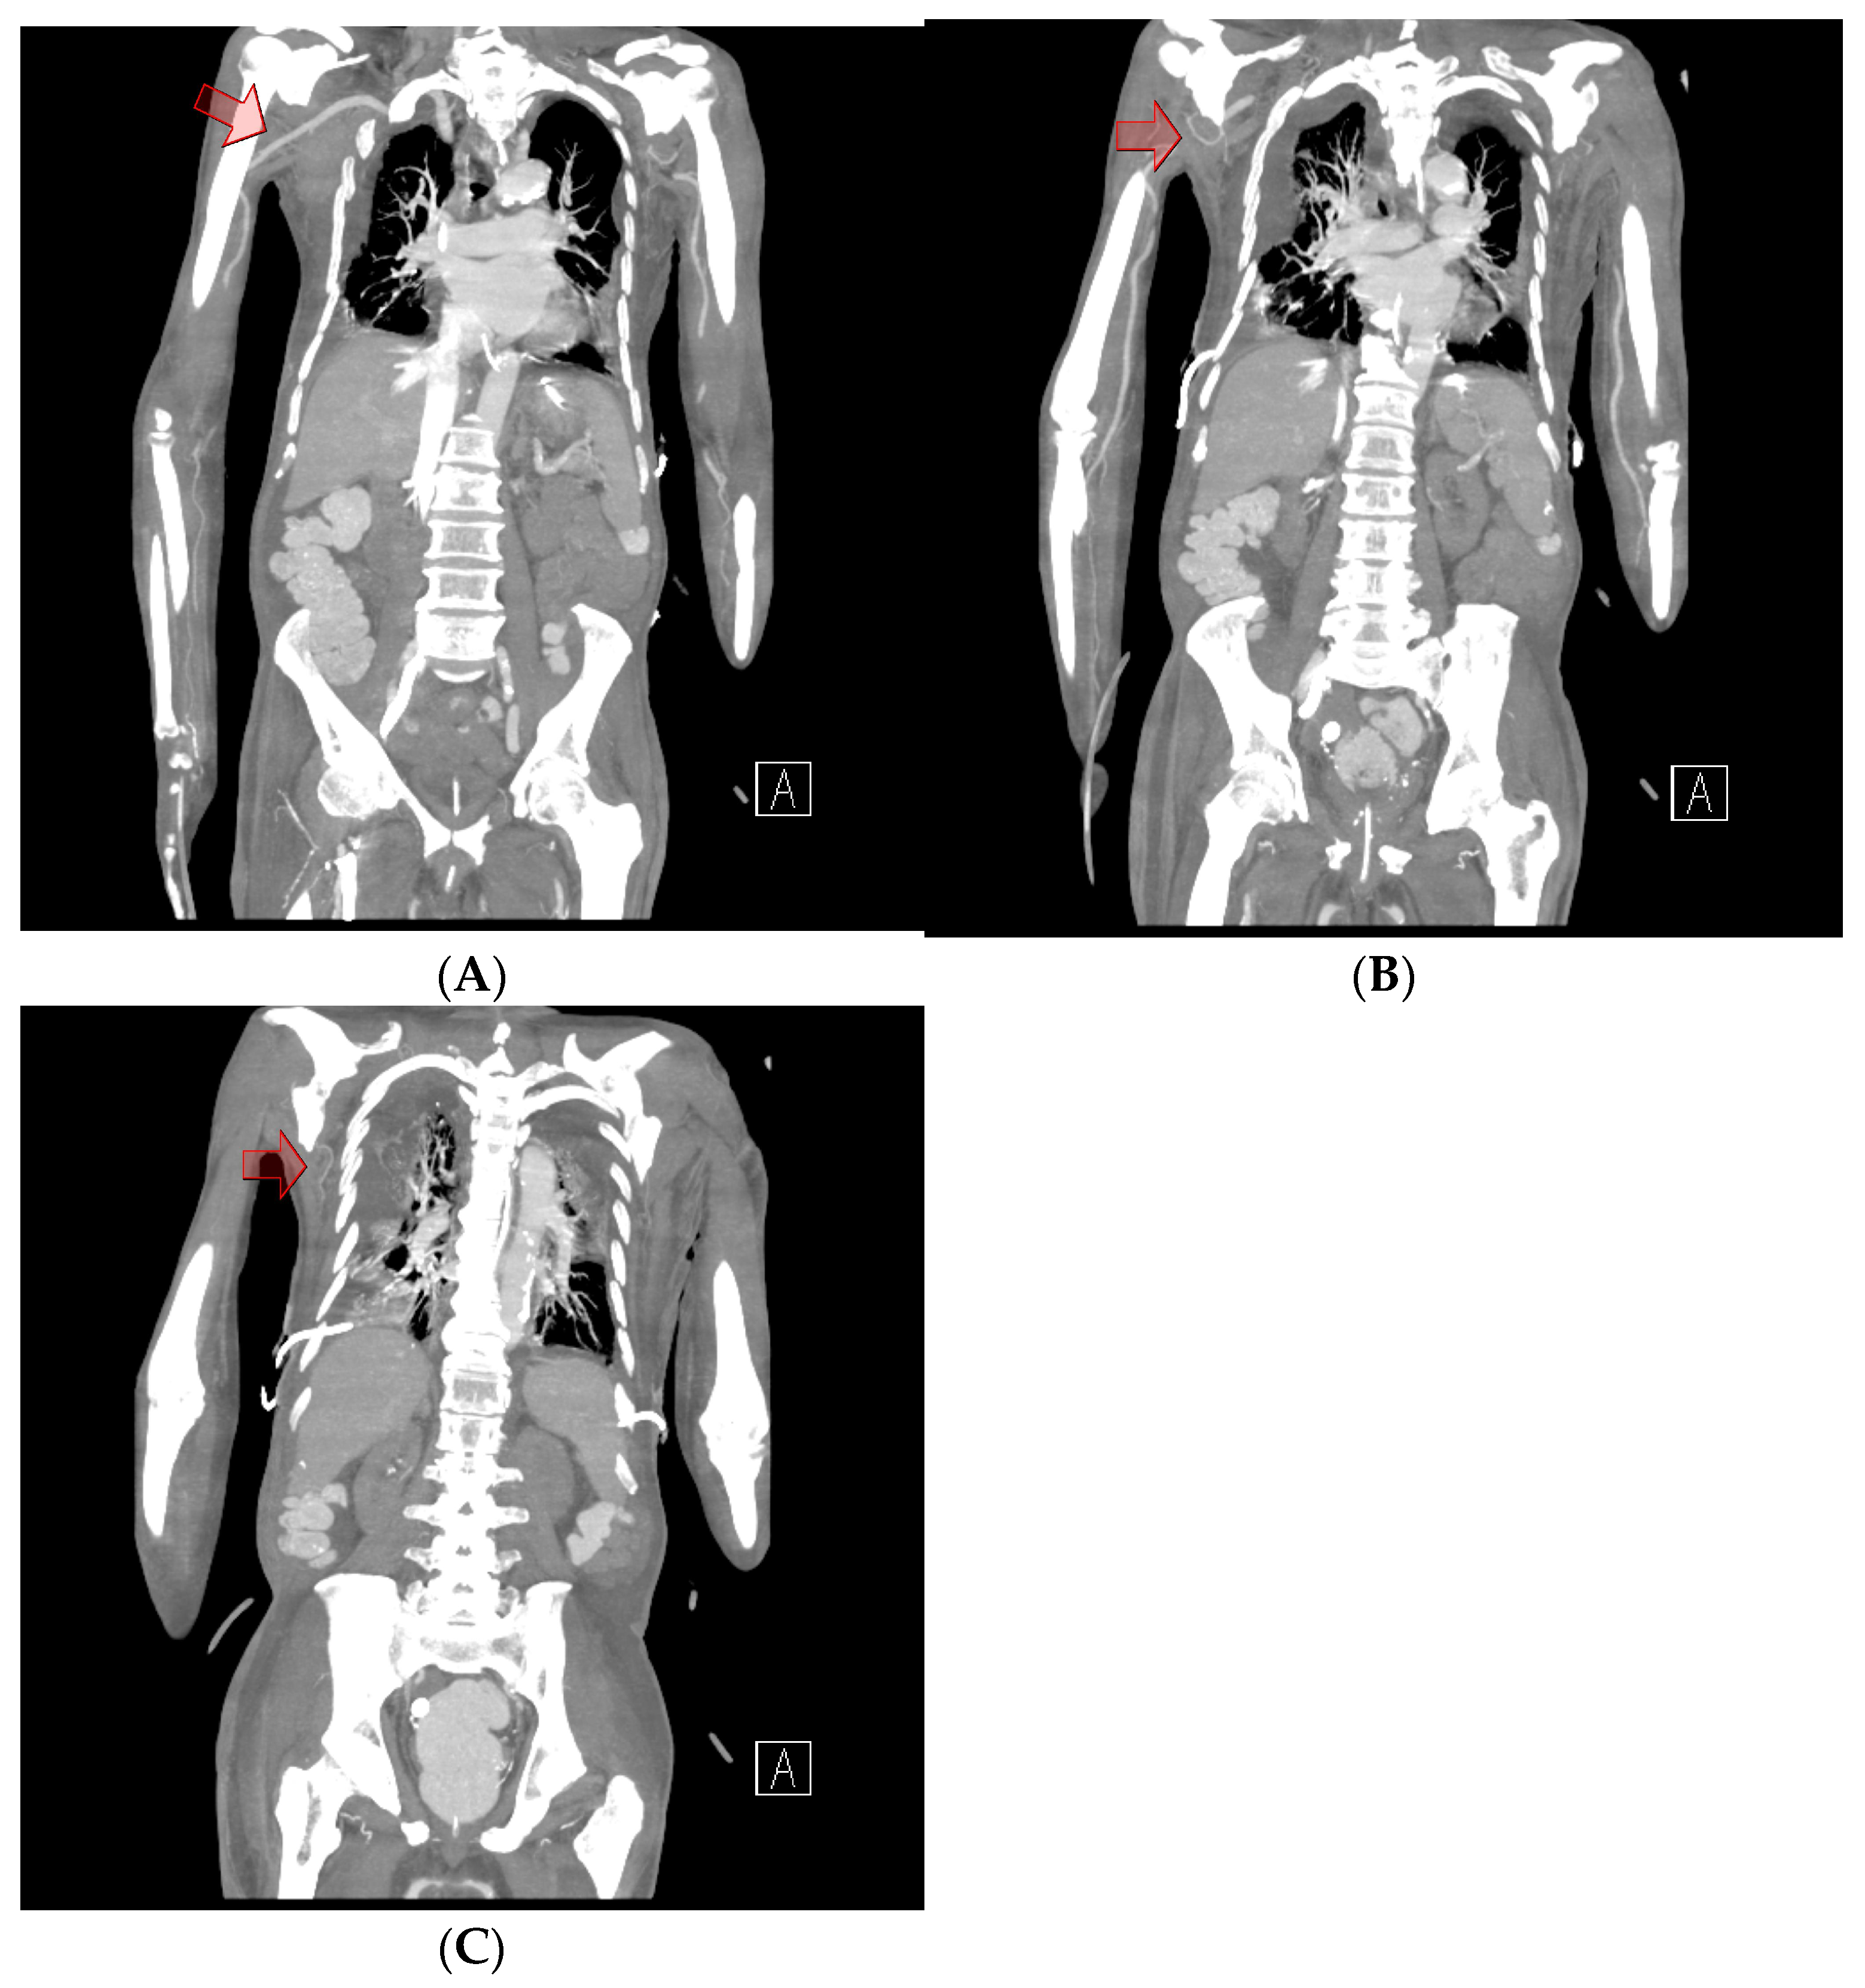

Chest computed tomography (CT) angiography revealed a newly formed 18.7 × 13.1 × 9.6 cm hematoma in the right upper anterior chest wall, with no signs of active bleeding or evidence of a pseudoaneurysm or malignant tumor (Figure 1 and Figure 2). On the fourth day post-onset, transarterial angiography was conducted via the right common femoral artery. Angiograms of the right subclavian artery, right internal mammary artery, and thoracic aorta showed no active bleeding, precluding the possibility of embolization. To manage the resulting anemia, 2 units of PRCs were transfused.

On the fifth day, surgical exploration revealed a large hematoma beneath the pectoralis major muscle. The hematoma had solidified and showed no signs of infection; culture results were negative. Bleeding was identified from a branch of the lateral thoracic artery within the deep portion of the pectoralis major muscle, as observed on CT angiography (Figure 3). The procedure involved removing the hematoma and ligating the vessel, followed by irrigation, placement of a closed suction drain, and primary closure. The surgery was completed with a mild compressive dressing (Figure 4).

Figure 2. Chest computed tomography angiography. (A) A coronal view shows intact vessel patency in the subclavian artery and axillary artery (red arrow), which could have contributed to the hematoma in the chest wall. (B) No extravasation or abnormalities were observed in the thoracoacromial artery (red arrow). (C) No abnormalities were observed in the main pedicle of the lateral thoracic artery (red arrow).